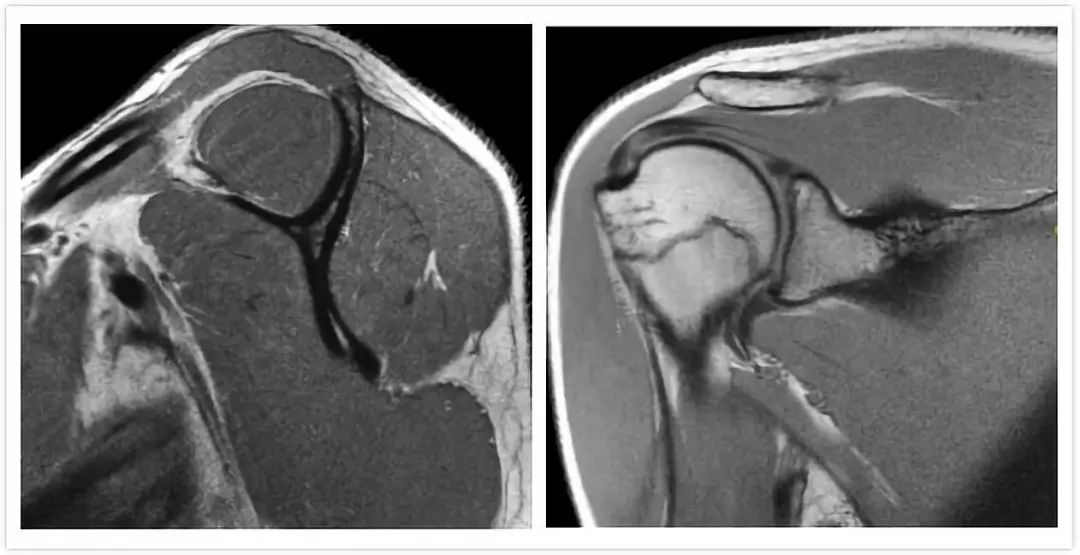

教你看核磁片子 西瓜视频